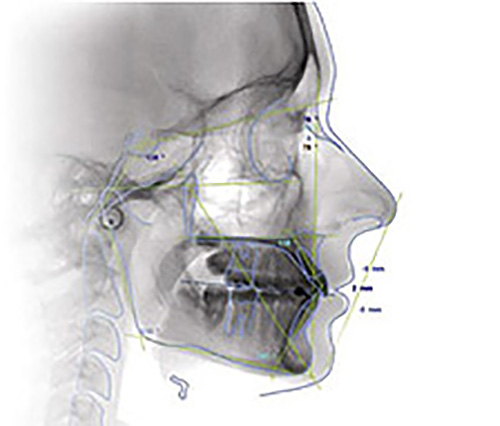

Si tratta di una radiografia della testa di profilo che permette una dettagliata visione delle strutture dentali e delle loro basi scheletriche di sostegno (mascellari) rispetto al contesto generale cranio-facciale, evidenziando perfettamente i profili dei tessuti molli (naso, labbra e mento). Fondamentale a scopo diagnostico in ortodonzia, poiché da questa radiografia l’ortodonzista elabora un Tracciato cefalometrico, ovvero un’analisi dei rapporti di reciprocità e posizione di importanti punti anatomici, cioè una serie di misurazioni fatte a partire da punti cranici.

Grazie a queste misurazioni, l’ortodontista può capire se la posizione reciproca delle ossa mascellari è corretta o meno, per esempio se la mandibola sta “troppo avanti” o “troppo indietro” rispetto al mascellare superiore, e se i denti hanno una posizione corretta rispetto alle ossa. Un esame indispensabile nei casi di malocclusione per la corretta diagnosi e per l’impostazione del piano di trattamento ortodontico.

L’esame si esegue utilizzando un apparecchio radiografico specifico munito di un craniostato che permette di posizionare il cranio del paziente in una precisa posizione al fine di rendere ripetibile l’esame a distanza di tempo per successive comparazioni. L’apparecchio è in grado di ottenere teleradiografie in diverse proiezioni (latero-laterali, antero-posteriori, postero-anteriori) per lo studio ortodontico dei bambini e degli adulti.

Il posizionamento del paziente è garantito da un supporto frontale e da due ogive igienizzate che devono entrare nel meato acustico esterno. Il paziente viene invitato ad assumere una posizione di postura naturale. Mantenendo i denti stretti e le labbra morbide dovrà restare immobile per 8 – 15 secondi.

Lo studio esegue l’esame con la Tecnica Digitale Diretta con Sensore CCD ad Alta Risoluzione che durante l’acquisizione visualizza in tempo reale le immagini a monitor. Le caratteristiche evolute della sorgente dei raggi e la rielaborazione digitale dell’immagine ottenuta mediante computer consentono di ottenere immagini ad elevato valore diagnostico con una dose di radiazioni al paziente inferiore del 50-70% rispetto alla tecnica con pellicola tradizionale.